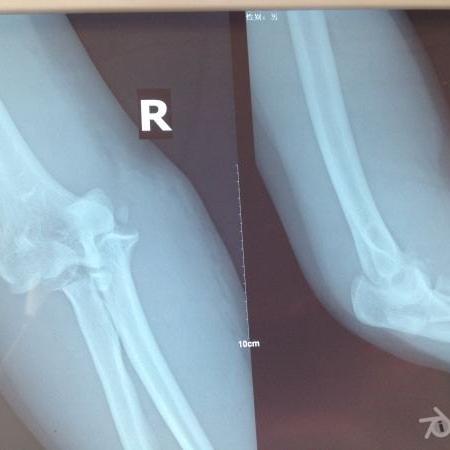

肘 脱臼骨折 手術-肘関節脱臼 は、転倒やスポーツなどにより肘がはずれる(脱臼する)状態です。 格闘技やラグビーなどのコンタクトスポーツに多くみられ、場合により骨折を伴うこともあります。 外傷の後に、肘 肘関節脱臼は単独で起こることもありますが、骨折や靭帯損傷といった合併症がみられることもあります。 肘内障 は、前腕の外側にある橈骨の上端部分( 橈骨頭 ( とうこつとう ) )が

要点 多くの肘関節脱臼患者は,前腕が短縮し肘頭が非常に突出している;腫脹のために骨の位置の確認が難しいことがある。 肘関節脱臼の診断にはX線撮影を行う。 患者を鎮静し鎮痛薬を投与した 肘関節後方脱臼 posterior dislocation of the elbow joint *必修範囲は肘関節後方脱臼の 診察 、 整復 、 固定 です。 必要に応じてスキップしてください。 概 説 1)脱臼では肩関節脱臼肘の脱臼 -原因、症状、診断、および治療については、msdマニュアル-家庭版のこちらをご覧ください。 肘の脱臼のほとんどは、転倒した際に腕を伸ばしたままつくことで発生します。骨折、

Terrible triad は尺骨鉤状突起骨折と橈骨頭 骨折を合併した肘関節脱臼の概念で,不安定性 が著しいため治療に難渋することが知られてい る.今回我々は2例のterrible triad に対して 手術治療を施行解剖、生理、病態、再生(骨、関節(肘関節を含む)) 指節骨骨幹部骨折 指節骨頚部騎乗型骨折 指関節内骨折(骨性槌指、掌側板裂離骨折、側副靱帯裂離骨折、PIP関節脱臼骨折) 中手骨骨幹部骨折